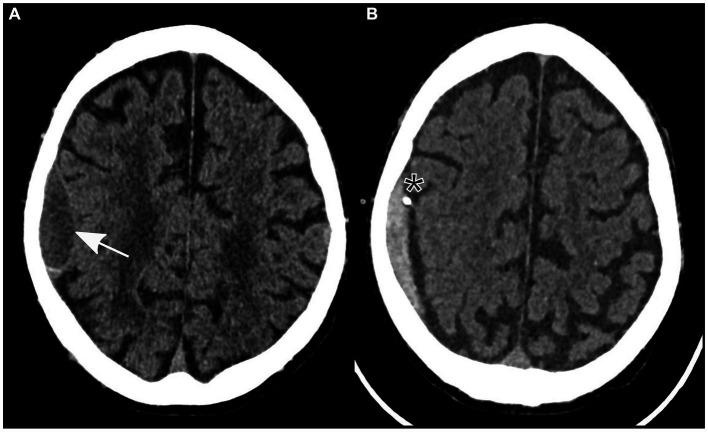

Case report: Concurrent low-volume subdural hematoma and ipsilateral ischemic stroke presenting as capsular warning syndrome: a complex case with anticoagulation dilemma and dual pathology.

An 83 years-old male patient initially presented with acute dyspnea, raising the suspicion of pulmonary embolism. After exclusion of pulmonary embolism through CT angiography, the patient experienced a sudden onset of left-sided hemiparesis without prior history of head trauma but with chronic intake of apixaban due to atrial fibrillation. Subsequent cranial CT tomography revealed a small right parietal subdural hematoma. After reversal of the anticoagulation therapy, surgical evacuation of the subdural hematoma was successfully performed. However, in the postoperative period, the patient developed new neurological symptoms that could not be explained by the reduced size of the subdural hematoma on a follow-up CT scan. Cranial MRI revealed the coexistence of acute ischemic stroke in the right corona radiata. The recent surgical procedure precluded guideline-recommended stroke treatment.

This case underscores the complexities of diagnosing and treating concomitant small volume subdural hematoma and ischemic stroke, especially if the latter occurs in the corona radiata resulting in fluctuating symptoms known as "capsular warning syndrome." Reversal and secondary discontinuation of anticoagulant therapy for surgical intervention highlight the inherent risk of thrombotic events in anticoagulated patients. The development of tailored treatment strategies requires a multidisciplinary approach, and further research and guidelines are required in similar complex scenarios.